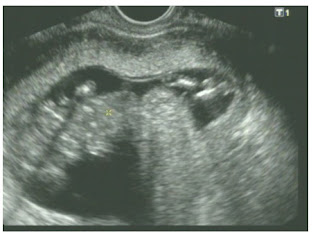

Agora vou postar umas fotinhas do bebe com 17 semanas e com 22 semanas

17 semanas, é menino mesmo, rs

Ele tá lá dentro com 17 semanas

Seus traços, já com 22 semanas.